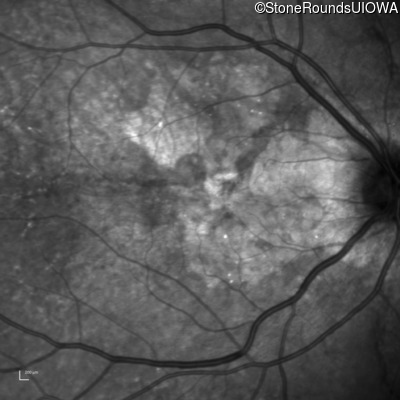

Infrared Fundus Photograph - Left - 20/20 -1

Exemplar